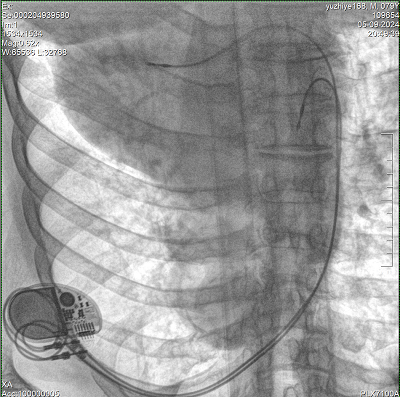

具備血管造影及數(shù)字減影(DSA)、路徑圖(Road-map)、透視、攝影等功能。 廣泛適用于介入科、血管外科、腫瘤科、消化內(nèi)科及骨科等多個(gè)臨床科室,典型應(yīng)用包括:TACE(肝腫瘤栓塞與化療灌注術(shù))、心臟起搏器置入術(shù)、四肢動(dòng)脈造影術(shù)、下肢靜脈濾器置入術(shù)、ERCP(經(jīng)內(nèi)鏡逆行胰膽管造影術(shù))等。

設(shè)備搭載自主研發(fā)的大功率高壓發(fā)生器、高熱容球管與大尺寸平板探測(cè)器,配合先進(jìn)圖像處理算法及高效冷卻循環(huán)系統(tǒng),能夠在長時(shí)間手術(shù)過程中持續(xù)輸出高清圖像并保持幀率穩(wěn)定。